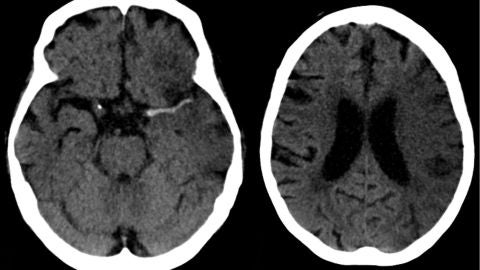

Entrevistamos a la presidenta de la Federación Española del Ictus, Carmen Aleix, ya que el día 29 de octubre se celebra el día mundial de esta enfermedad. Hablamos con ella de los síntomas previos que pueden darse y alguno de ellos son "visión borrosa, pérdida de sensibilidad de medio cuerpo y dolor súbito de cabeza" afirma Aleix. Las mujeres son más vulnerables a sufrirlo que los hombres y nos explica que "no se sabe por qué", además conocemos que "entre personas de 40 y 50 años es muy habitual que se dé".